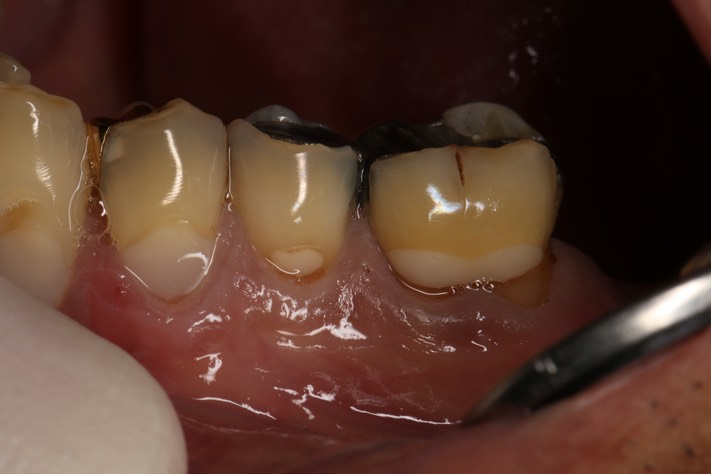

Frank Fukuda #19-20 buccal pre-op